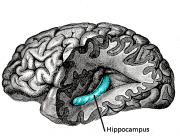

| 2021年7月26日 (一) 18:33 | Gray739-emphasizing-hippocampus.png (文件) |  |

263 KB | 77921020 | Uploaded with SimpleBatchUpload | 1 |